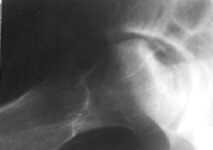

This 12 year old girl sustained a right femoral neck fracture by falling from a balcony(image 1). After 2 weeks of bed-rest, she was started walking with crutches. She completely returned to normal activities 6 months after the trauma. She was beginning to complain of the right hip pain 2 years after the trauma(image 2 & 3).